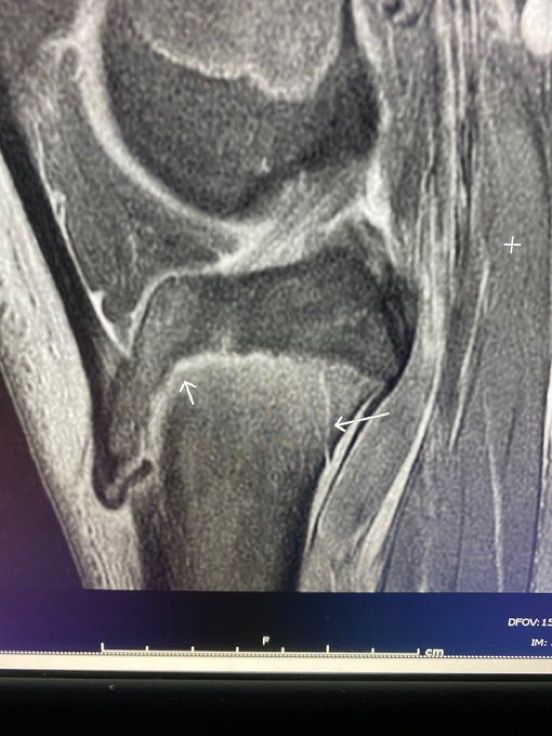

Salter-Harris type 2 fracture with stripped periosteum of the ATT. Note that the periosteum is displaced into the physis. A first for me.